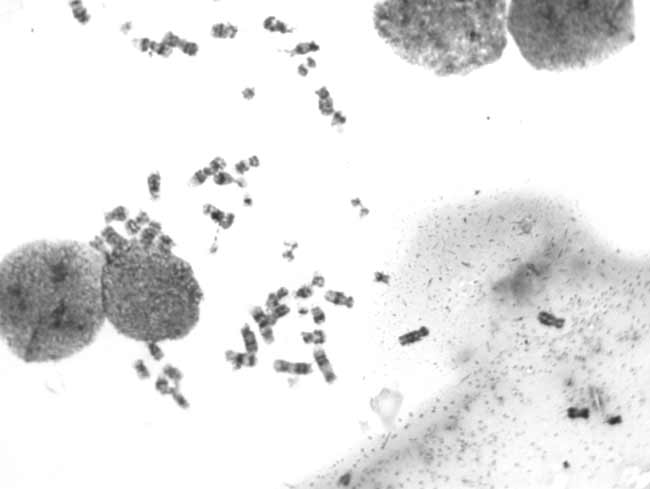

Should be the requirements of our customers, the Tucson special will be two high sensitivity CCD (TCC-1.4HICE (black and white) /TCC-1.4CHICE (color), in the biological study of microscopic images taken by chromosome released, welcome everyone to share.

Taken by Tucsen TCC-1.4H